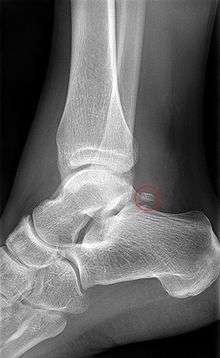

Talus - inferior view- Lateral view of the human ankle, including the talus